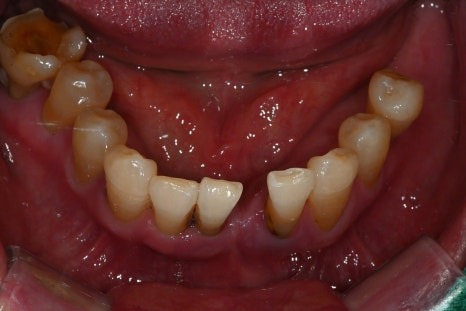

수술 후 4개월

수술 후 6개월 후 보철완료

치료 전 / 치료 후

치료 후